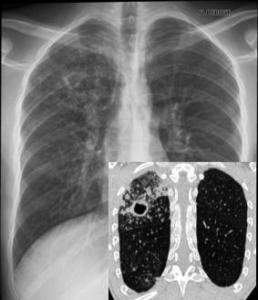

Oran - La maladie fait toujours des victimes: Une campagne contre la tuberculose A Oran, notamment dans les milieux sociaux défavorisés, le bacille de Koch fait toujours des victimes et il est à l'origine de trois à cinq décès par an.